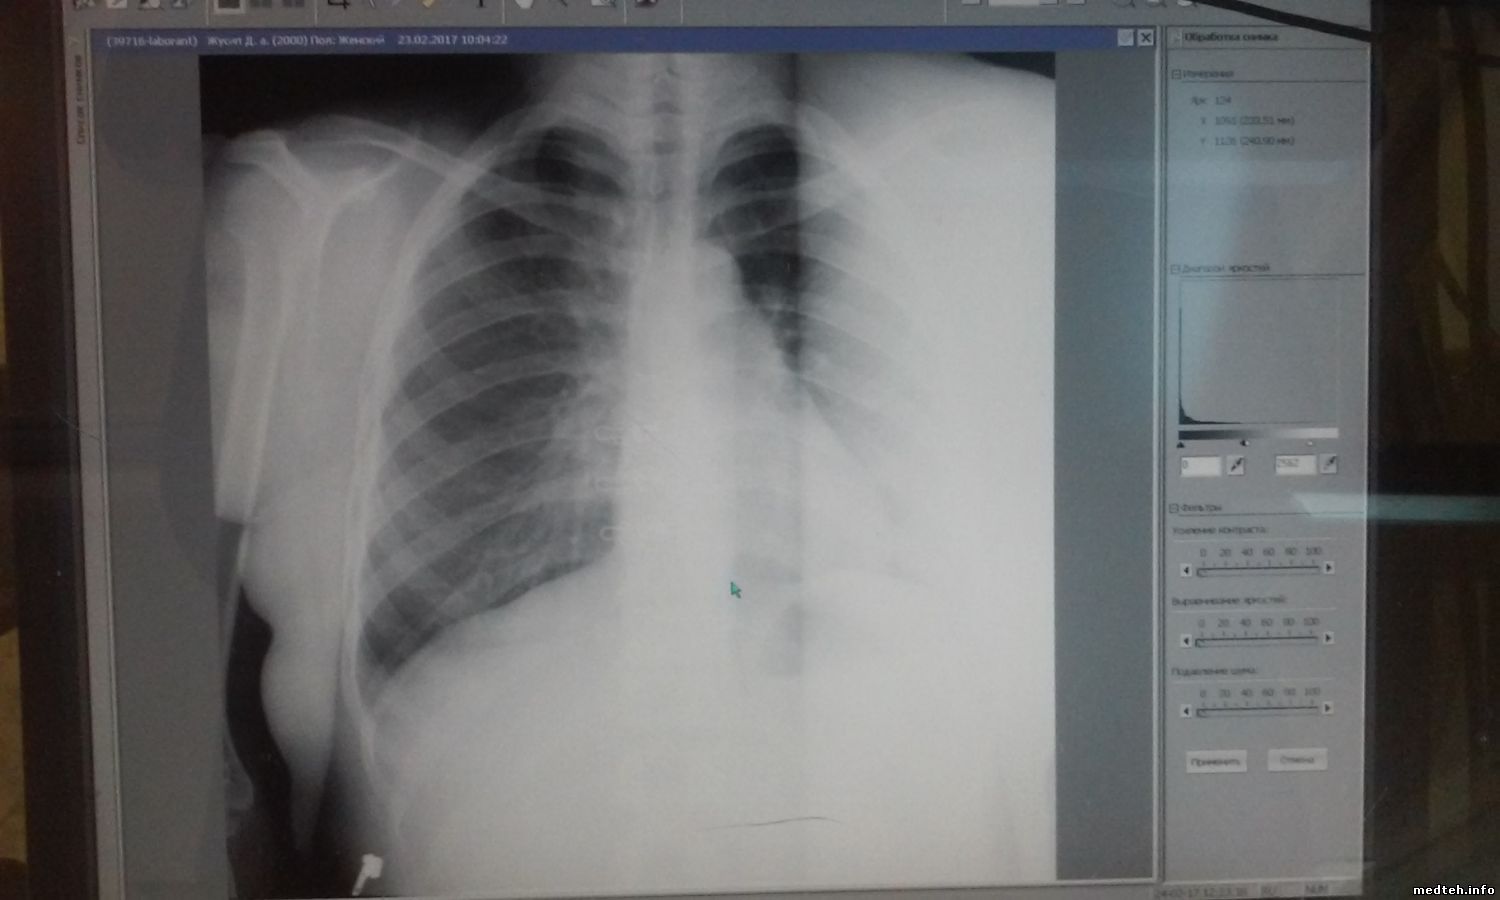

Привет всем... У меня проблемы с флюрографом Про-Скан 2000:

1: 3-4 сантиметровая полоска на правым участке снимка, доктор из за этого, снимка не читает, ибо мешает...тд тп

Делаю калибровку детектора и трубка, полоска изчезает временно, после 30-40 снимков появиться опять...

Сделали все возможные варианты ремонта, но все без результатно. Скажите что я пропустил ???

0288424.jpg (94.0 Kb)